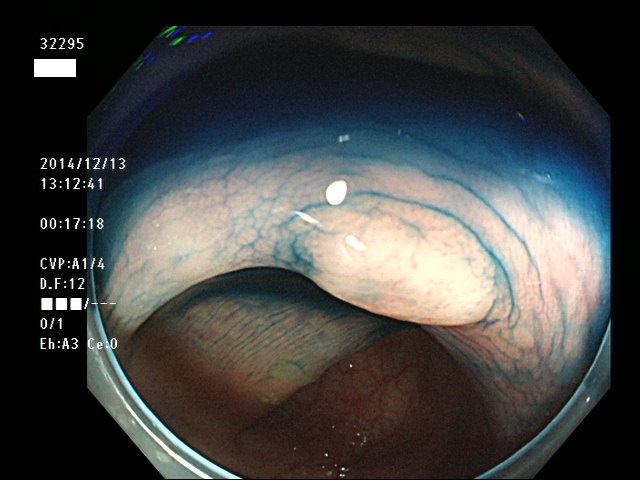

上記100名より抽出した平坦・陥凹型腺腫(=癌化の危険が高いが見落としやすい病変)の内視鏡写真